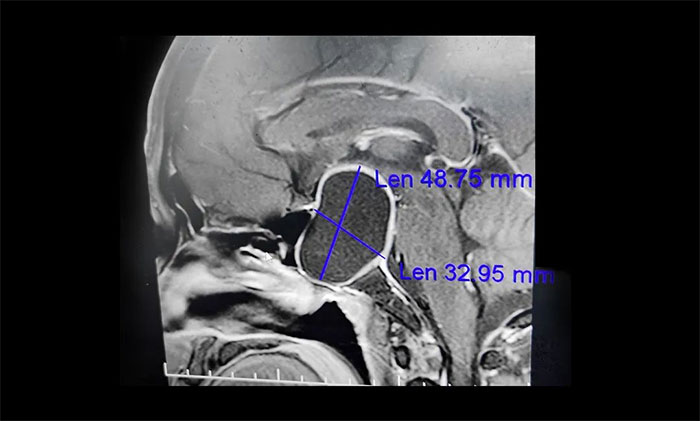

▲垂体大腺瘤伴囊变,压迫视神经,导致视野缺损、视力下降

“医生,我已经做了白内障手术,怎么眼睛还是看不清东西呢?”半年多前,67岁宋阿姨的因视力模糊和下降到眼科就诊,被确诊为右眼白内障。当地眼科医生为宋阿姨进行了白内障手术。本以为手术后,视力便可慢慢恢复正常。谁料,右眼视力却愈发“不好使”,左眼的视力也下降明显。通过对宋阿姨眼睛的复查,虽然白内障得到改善,但患者视力仍很差,双眼外侧的余光变窄,因此医生高度怀疑他视力下降的原因可能跟脑部病有关,因此建议宋阿姨到神经内科做进一步检查。最终查出4公分大的巨大垂体瘤。